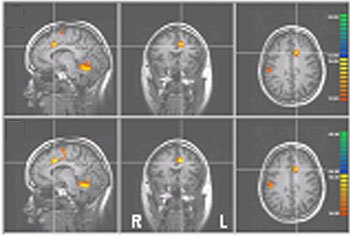

These fMRI brain scans show various levels of activity (colors) in a part of the brain called the rostral anterior cingulate cortex.

Using a brain-scanning machine called an fMRI scanner, the scientists were able to see that this level of pain sparked a lot of activity in a part of the brain called the rostral anterior cingulate cortex.

Next, eight of the volunteers went through brain training. Scientists hooked them up to machines that allowed them to see what was going on in their own rostral anterior cingulate cortexes. An image of a flame grew when there was a lot of activity there and shrank when there was less.

After 39 minutes of practice, the researchers found, volunteers were able to control the size of the flame and, hence, their pain levels, even with the same intensity of heat on their legs. Mental exercises, such as thinking about something besides the pain, seemed to help.